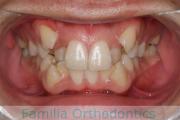

No.22V-409

- 叢生

- 16歳

- 女性

- 抜歯部位

- 上:

- 44

- 下:

- 8|58

- 主な使用装置:

- FEA

- 治療にかかった費用:

- 86万円

八重歯を治したいということで来院されました。下あごの左ずれのある上顎前突(出っ歯)・叢生(でこぼこ)でしたので、上は左右から、下はで左のみ小臼歯を抜歯して、歯科矯正用アンカースクリューとマルチブラケット法にて治療を行いました。2年強、30回程度の通院が必要でした。

上下とも前歯の叢生(でこぼこ、凹凸、ガタガタ)があるため、保定を怠ると後戻りのリスクがあります。